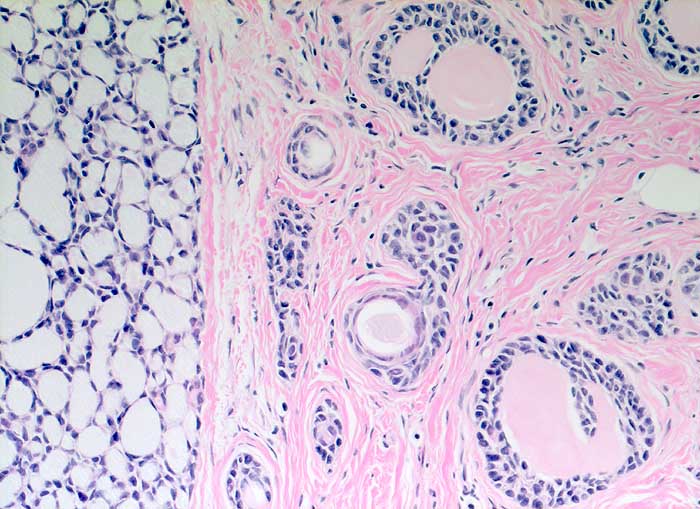

Adenoidzystisches Karzinom

Kribriforme Tumormasse. Die Hohlräume sind gefüllt mit mucoidem Material oder eosinophilem amorphem Material.

Adenoidzystische Karzinome kommen vor allem im Bereich der Speicheldrüsen vor, treten aber auch in anderen Organen auf. Sie machen weniger als 0.1% - 0.2% der Mammakarzinome aus.

Histologie

200